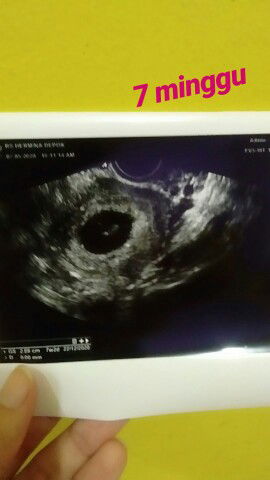

Usg vagina

usg di perut belum terlihat, jd usg vagina keliatan kandungan 7minggu.. hitungan hpht harusnya 10minggu.. bismillah , semoga anak saya sehat selalu